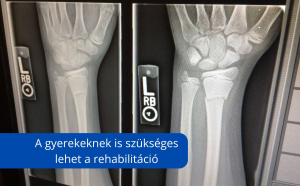

Mit érdemes tudni, ha eltörik a gyermeked keze vagy lába?

Sokszor a gyerekek számára nem ajánlanak gyógytornát – mondván, hogy fiatal szervezetük úgyis „rendbe jön” magától. Ez azonban nem minden esetben van így. A hetekig nem használt végtag mozgásmintája megváltozhat, ami hosszabb távon is okozhat panaszokat, főként, ha a gyermek sportol vagy sokat mozog.

A gyerek nem kis felnőtt – de a gyógytornára neki is szüksége lehet